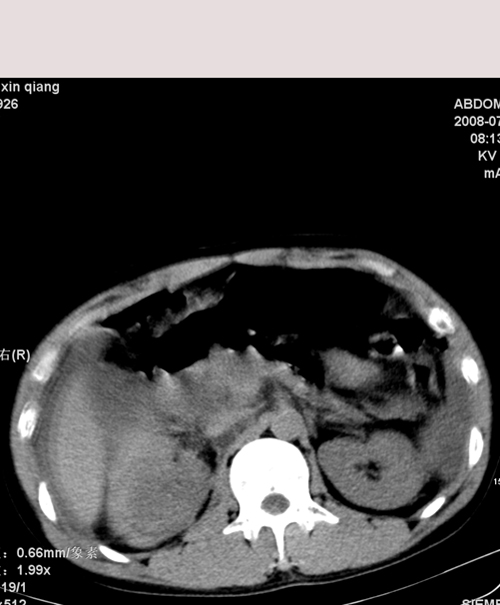

以下是引用随光逐影在2008-7-15 11:18:00的发言:[br]考虑为:1)腹部空腔脏器穿孔。2)右肾破裂并肾包膜下血肿,肾盂积血。3)腹水(血)。

以下是引用muzi888在2008-7-15 10:45:00的发言:[br]大量腹腔积液,气腹,肾皮质弧形高密度影,诊断;1 空腔脏器穿孔 2 右肾包膜下血肿

以下是引用yangyudong333在2008-7-15 12:06:00的发言:[br]考虑为:1)腹部空腔脏器穿孔。2)右肾破裂并肾包膜下血肿,肾盂积血。3)腹水(血)。